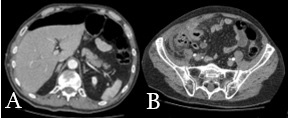

Internado por síndrome medular parcial, instaló dolor abdominal brusco en epigastrio que irradiaba a fosa ilíaca y flanco derecho. Cursó en apirexia, sin alteraciones del tránsito digestivo. Del examen físico se destacaba un abdomen con elementos de irritación peritoneal en hemiabdomen derecho. De la analítica se destacaba leucocitosis 30.000. Sin disfunciones (Fig.1). Se realizó tomografía de abdomen y pelvis que evidenció neumoperitoneo (Fig.1. A). En relación al ciego, imagen tubular con gas en su interior (Fig.1. B). Múltiples adenomegalias mesentéricas.

Fig.1: A) Evidencia de neumoperitoneo. B) imagen tubular en relación al ciego

Fuente: del autor.